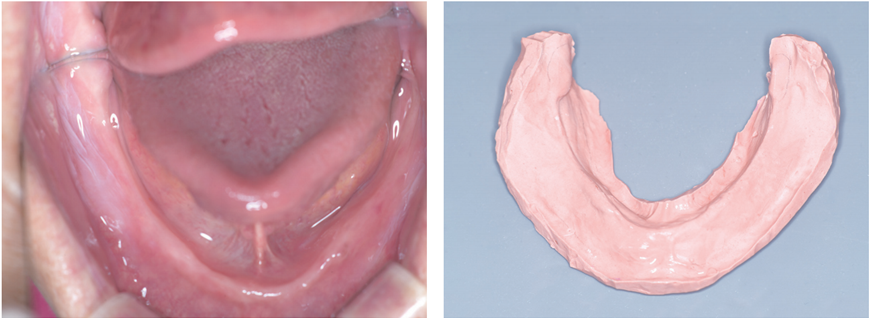

하악은 치조정이 매우 낮고 협측으로 너무 평탄하다. 하악 협측 부위에서 부착치은이 많이 부족하다.

하악 치조제 상태가 너무 열악합니다. 부착치은이 부족하고 유리치은이 치조제 절반을 차지하고 있습니다. 믿을 곳은 mylohyoid ridge 하방뿐입니다. Mylohyoid ridge 하방을 최대한 확보하기 위해 1차 인상에서 혼수비를 적게 해서 압박을 가하는 인상이 필요합니다. 물론 alginate wash impression이 답이지요.